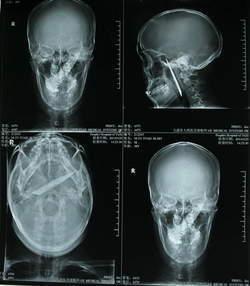

À son grand étonnement, les médecins lui ont dit qu'il avait un objet métallique de 10,5 cm dans la tête. La lame d'un couteau.

Mais la lame avait disparue. Celle-ci a désormais été retrouvée et retirée avec succès de la tête de la victime.